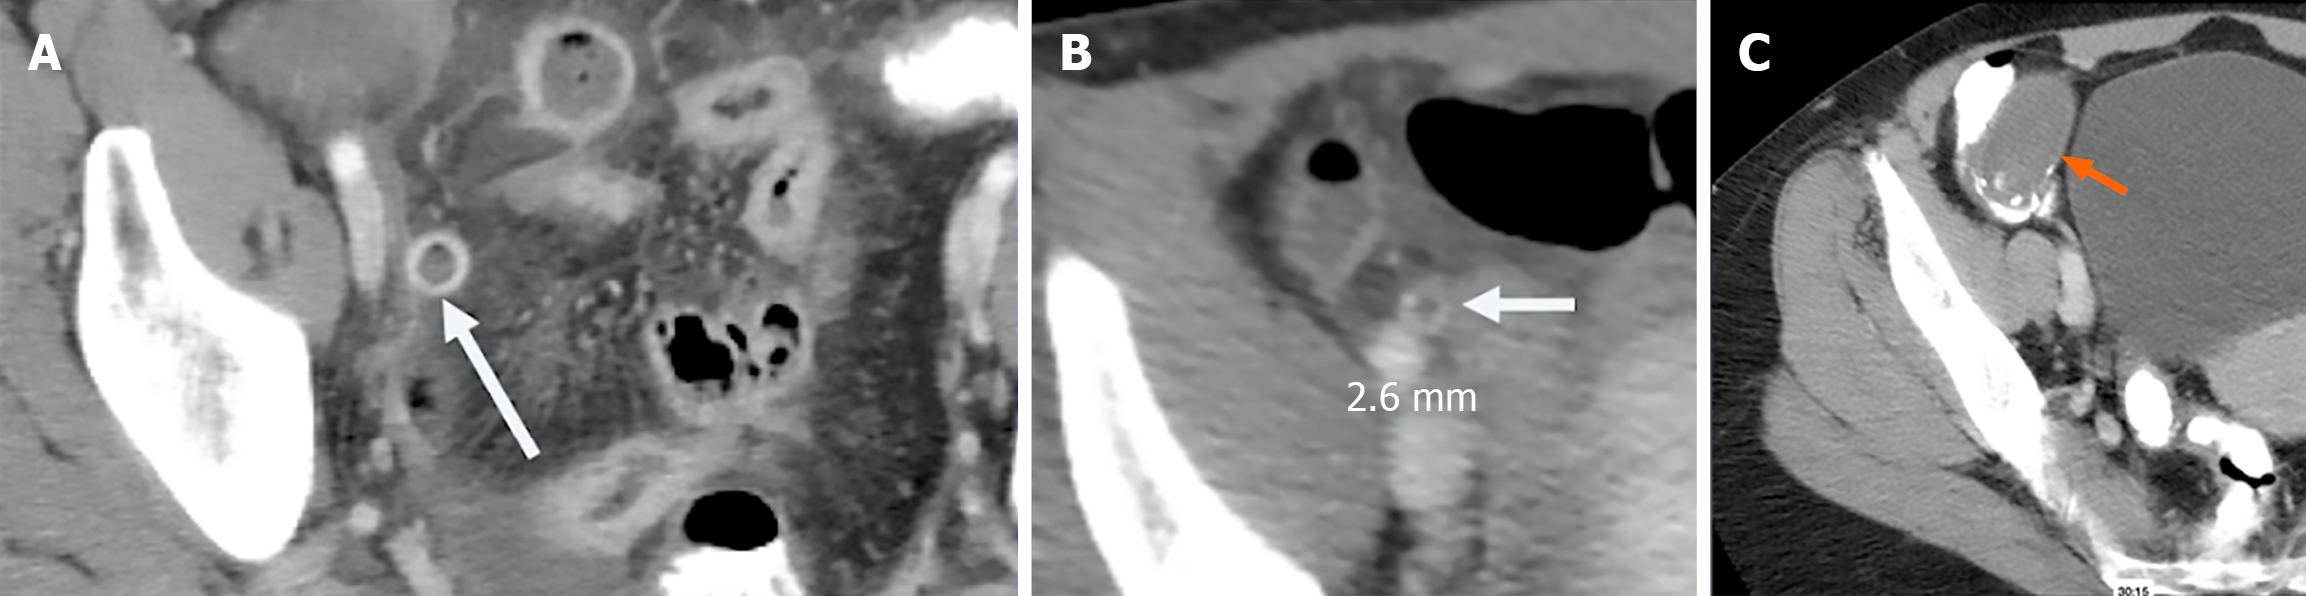

Among these secondary signs, peri-appendiceal fat stranding and fluid collections signify localized inflammation (Figure 1). The stranding appears as bright, inflamed fat surrounding the appendix and often correlates with symptom severity[10]. Wall thickening greater than 3 mm and hyperenhancement following contrast administration are additional indicators of appendicitis (Figure 2A)[11]. A particularly specific but less common finding is the presence of airless, low-attenuation fluid within the lumen (Figure 2B). This fluid type is rare in normal appendices and may signify early mucosal involvement. A threshold of 2.6 mm of fluid within the appendix has shown strong diagnostic performance[9,12].

Figure 2

Figure 2 Image. A: Computed tomography showing appendiceal wall hyperenhancement. White arrow: Inflamed, enhancing appendiceal wall consistent with acute appendicitis; B: Computed tomography showing airless, low attenuation fluid in the lumen, a frequently useful sign in early appendicitis. White arrow: Fluid-filled, non-aerated lumen measuring 2.6 mm, indicating early mucosal inflammation; C: Distended appendix fluid filled, curvilinear calcifications at base with airless low attenuation fluid, which was identified as a mucocele (orange arrow).

CT, while powerful, is not infallible. Missed diagnoses may result from perceptual errors or from overreliance on the presence of luminal air to exclude appendicitis[15]. In reality, up to 31% of confirmed appendicitis cases may contain intraluminal air. Conversely, false positives may arise from conditions such as mucoceles, mucinous cystadenomas, lymphomas, or cecal obstruction. These pathologies can mimic an inflamed appendix due to overlapping imaging features such as distension and fluid content[16,17]. When you see airless low attenuation fluid-filled appendices, it is imperative to look at the cecum for obstruction Figure 2C.